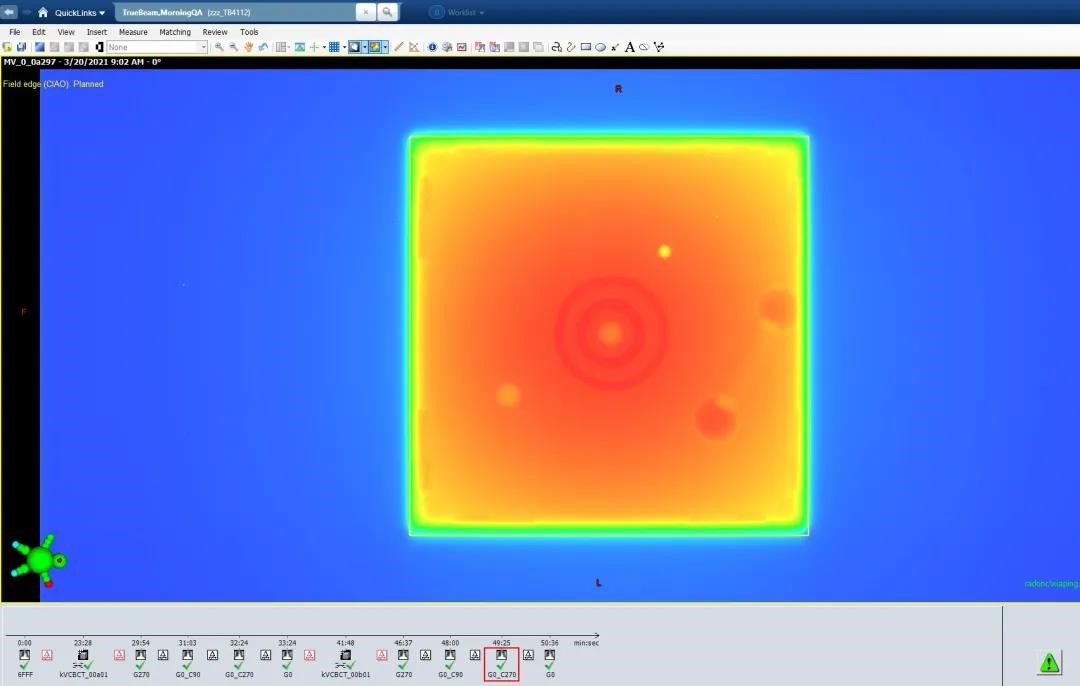

胶片剂量验证

Potal Dosimetry剂量验证